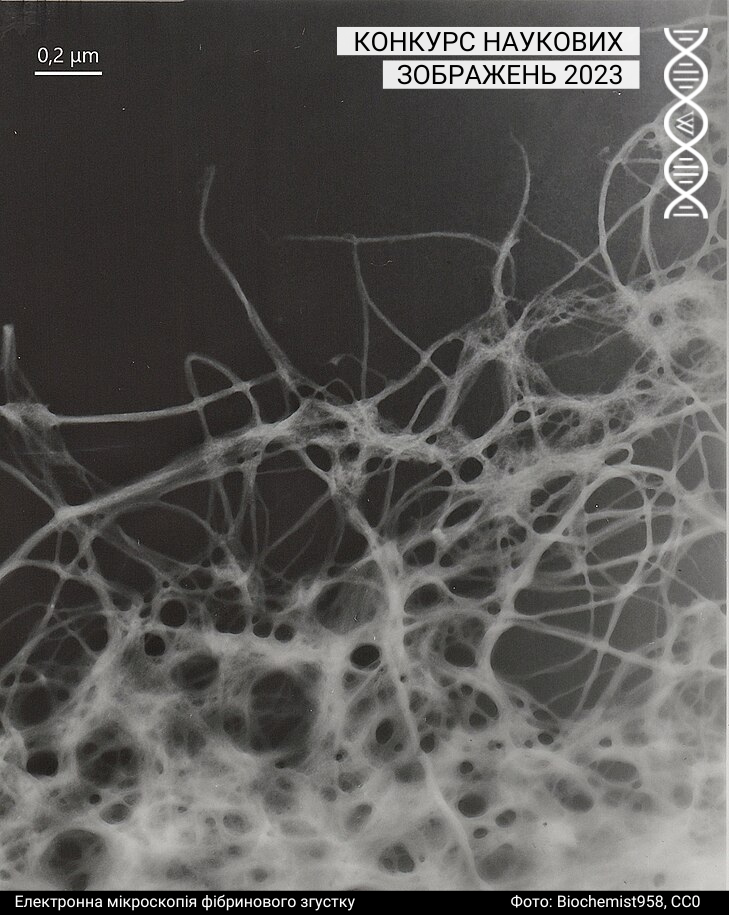

Мікроскопія

Під цю категорію підпадають світлини, зроблені за допомогою різних методик мікроскопії. Минулого року до цієї категорії учасники та учасниці завантажили 43 фотографії.

Спеціальна відзнака журі

Журі призначили спеціальну відзнаку серії зображень однієї авторки: https://w.wiki/99qJ, https://w.wiki/99qK, https://w.wiki/99qL, https://w.wiki/99qM